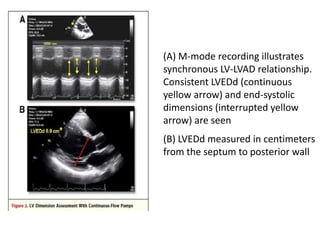

(A) M-mode recording illustrates

synchronous LV-LVAD relationship.

Consistent LVEDd (continuous

yellow arrow) and end-systolic

dimensions (interrupted yellow

arrow) are seen

(B) LVEDd measured in centimeters

from the septum to posterior wall

(A) M-mode recordingillustrates synchronous LV-LVAD relationship. Consistent LVEDd (continuous yellow arrow) and end-systolic dimensions (interrupted yellow arrow) are seen (B) LVEDd measured in centimeters from the septum to posterior wall